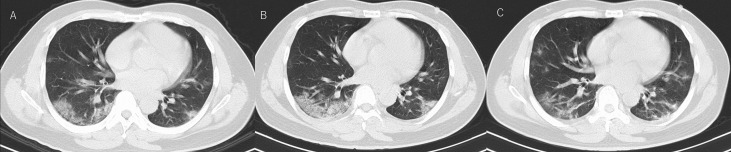

Fig. 2.

Chest CT images of Case 1 patient during hospitalization: A) Day 8 of his illness, peripheral ground-glass opacity and consolidation on both lower lobes. B) Day 11 of his illness, consolidation on the dorsal side increased in extent. C) Day 17 of his illness, consolidation on dorsal side tend to disappear, however new ground glass opacity appeared on right middle lobe and left S8.

On day 9 of his illness, oxygen saturation could not be maintained under nasal oxygen therapy, so high-flow nasal oxygen therapy was started at 40L/min and 40%, (Fig. 1-A). The RT-PCR result became negative on day 13 (Fig. 1-A), after which respiratory status improved and fever decreased. He was discharged on day 20 after confirming 2 consecutive negative RT-PCR results from oropharyngeal swab samples (Fig. 1-A), in line with the criteria for discharge in Japan. Chest CT findings gradually improved following the seroconversion of viral RNA to negative and improvement of general condition (Fig. 2). During hospitalization, we did not administer any antiviral or steroid therapy but provided only conservative and supportive care such as administering antipyretics and implementing measures to deep vein thrombosis. No symptoms suspect for recurrence of COVID-19 have been detected since discharge.